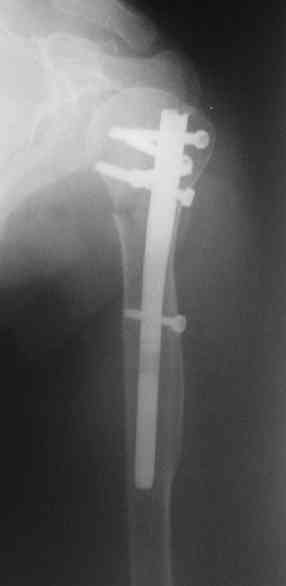

I am attaching the radiographs of the mother of a doctor. She has chronic renal failure for >10 years, diabetes mellitus and coronary artery disease. Age 62. She was offered the options of non-surgical management in a sling and surgery with a locking plate. She was given Tramadol for pain relief. Five days after injury, patient requested surgery, because of pain, inability to move without pain.

The reduction is not perfect. The patient is very small made, and it was difficult to bring the plate proximally without impingement in abduction.

Pain relief after surgery was early and sustained.